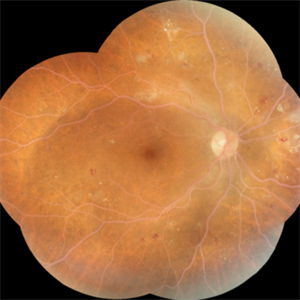

Retinal Detachment

Montage fundus photo of superior retinal detachment in right eye of a 45 year old male patient

Photographer: Dr.Maneesh Bapaye

Imaging device: Zeiss Fundus camera

Condition/keywords: montage fundus photo